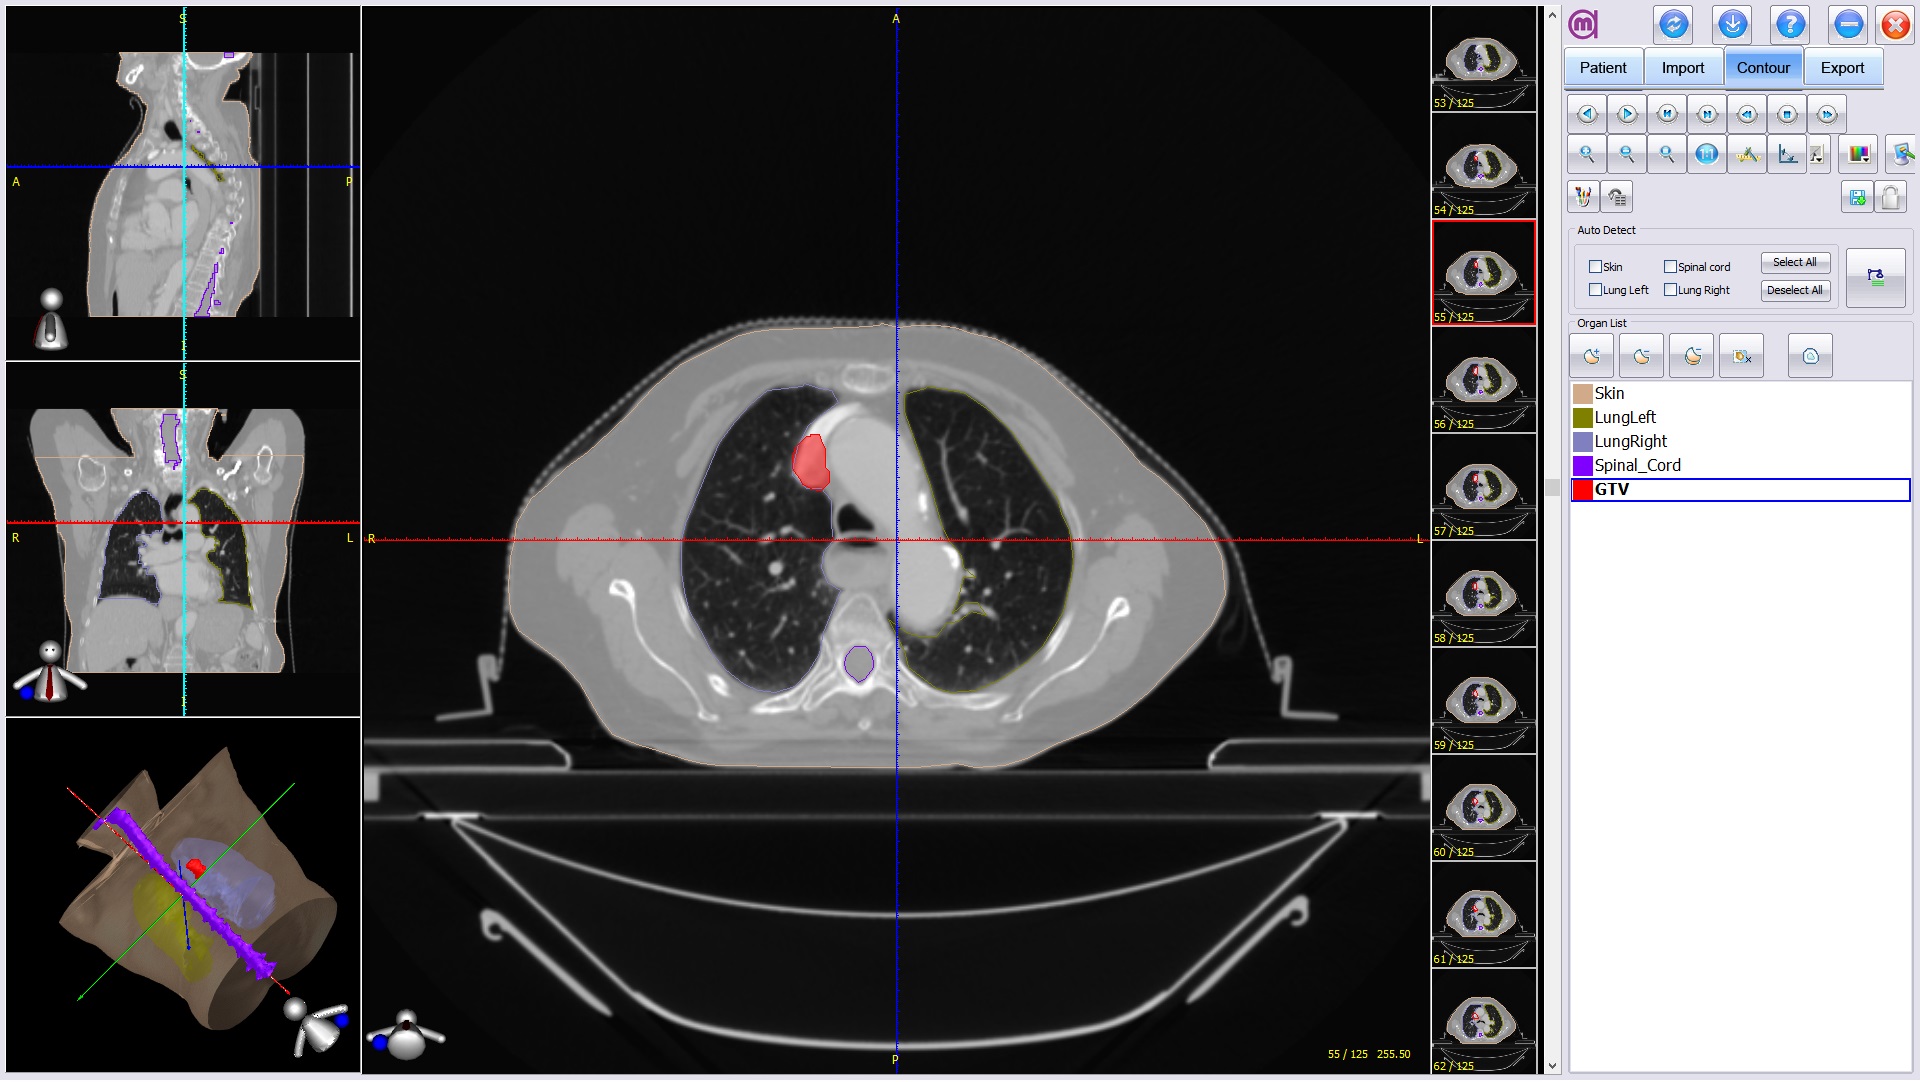

DMS的目标是成为放疗医生的全能移动助理。可以完成病人数据的管理,远程靶区和重要器官勾画和计划确认,DICOM网络连接,数据备份,云端存储等功能。适合安装在微软Surface Pro 3移动平板电脑使用,2160*1440高分辨率视网膜屏,触控操作,勾画时可以使用如钢笔一样灵活的感应笔。(兼容PC机工作站)。

靶区器官勾画

Surface Pro 3一机两用之平板使用方法,适合移动应用,查房,外出开会、讲演、学术交流时使用等